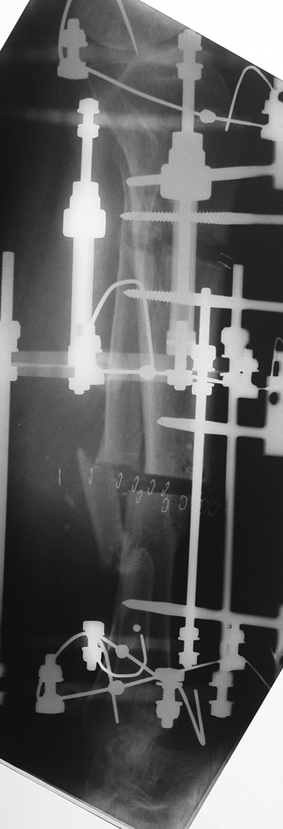

Appropriate radical debridement necessitates excision of all necrotic bone and soft tissues, and frequently causes instability at the involved extremity. The remaining bone and soft tissue defect has to be fixed and reconstructed. The distraction osteogenesis method of Ilizarov is used successfully for achievement of union, correction of the deformity, elimination of limb length inequality and reconstruction of segmental bone defects.

The duration of external fixation (external fixation index) depends on the amount of distraction required, and the extremity is prone to complications during this period. After the distraction phase is completed, the external fixator remains in place during the consolidation phase, which lasts twice as long as the distraction phase; but this period is hardly tolerated. If the external fixator is removed before sufficient consolidation is achieved, fractures, deformity and shortness will be the result. In our department, ‘lenghthening over nail’ method is used in order to decrease the external fixation index and increase patient comfort and activity level. In this method, the intramedullary nail is statically locked after the completion of the distraction phase, and external fixator is removed. The extremity is stabilized by the intramedullary nail during consolidation phase. In this way, complications due to long external fixation index or early removal of the external fixator are avoided.